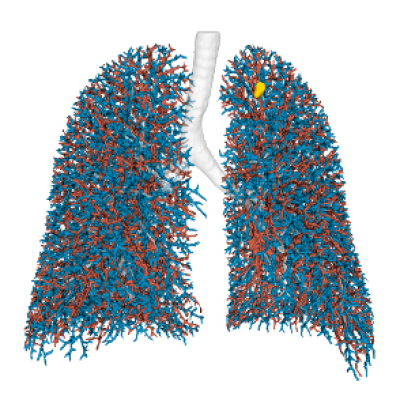

Pulmonary arteries & veins

Quantitative assessment

CT approximated perfusion defects

Quantitative assessment